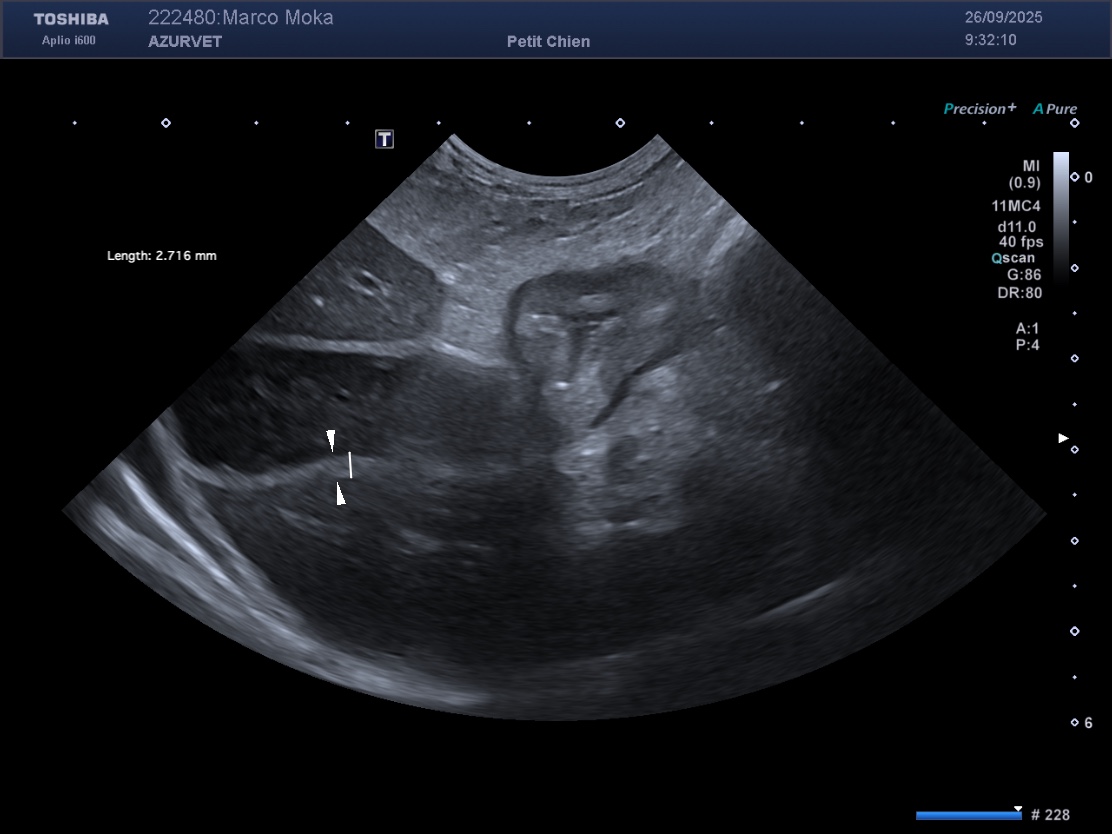

Figure 4 : thrombus dans l'artère iliaque externe G du Pinscher des figures 1 et 2. L'animal présentait une boiterie du membre pelvien G apparue de façon concomittabte aux troubles digestifs.

3) la recherche de thrombus artériel ou veineux (secondaire à la fuite de protéines anticoagulantes dans le tube digestif) : figure 4 et 5 ci dessous.